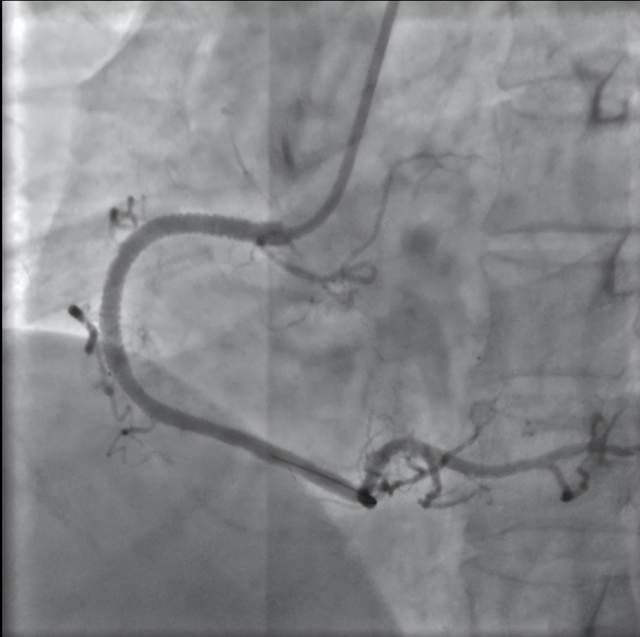

压面机切断面点师食指。3.5小时精细手术保住。武汉大学泰康临床学院、泰康同济(武汉)医院(简称泰康同济)骨科团队为患者李先生成功施行断指再植手术。患者断指血运稳定。高速运转的压面机几乎切断了他的右手食指。 为确保断指再...